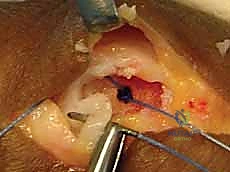

تعتمد استراتيجية العلاج التي يتبناها الأستاذ الدكتور محمد هطيف على درجة الإصابة، عمر المريض، مستوى نشاطه (رياضي محترف مقابل شخص عادي)، والوقت المنقضي منذ الإصابة.

| الدرجة الثالثة (Grade III) | تمزق كامل للرباط (انفصال تام). | ألم مبرح (قد يقل لاحقاً بسبب قطع الأعصاب الموضعية)، تورم شديد، كدمات واسعة، فقدان كبير لقوة القبضة. | عدم استقرار واضح (رخاوة شديدة). غياب نقطة التوقف عند اختبار الإجهاد. احتمال كبير لوجود "آفة ستينر". | تدخل جراحي حتمي ومبكر: لإعادة ربط الرباط بالعظم واستعادة استقرار المفصل، يليه تأهيل مكثف. |

يغطي الجانب الزندي للمفصل ما يُعرف بـ الوتر المقرب (Adductor Aponeurosis)، وهو عبارة عن غمد ليفي ضيق وقوي نسبياً. هذا الضيق له أهمية جراحية بالغة. عند حدوث تمزق كامل في الرباط الجانبي الزندي (UCL) من مكان ارتكازه، يمكن أن ينزلق الطرف الممزق من الرباط ويخرج من تحت هذا الوتر المقرب ليصبح محتجزاً فوقه.

بمجرد حدوث ذلك، يصبح الوتر المقرب حاجزاً مادياً يفصل بين طرفي الرباط الممزق، مما يجعل الالتئام الطبيعي مستحيلاً تماماً. هذه الظاهرة التشريحية المعقدة تُعرف طبياً باسم آفة ستينر (Stener lesion).

الأهمية السريرية: تُعد آفة ستينر علامة مميزة وحاسمة للتمزق الكامل في الرباط الجانبي الزندي، ووجودها يستدعي التدخل الجراحي الحتمي، حيث لا يمكن للعلاج التحفظي (الجبس) أن ينجح أبداً في وجود هذا الحاجز.